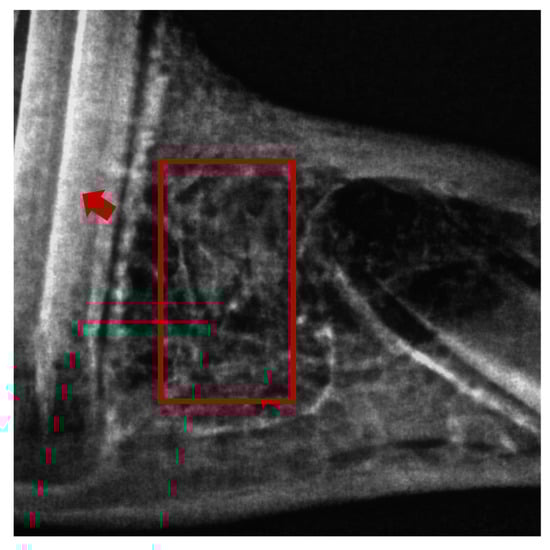

4.3. Surgical Procedure

4.4. Sample Collection